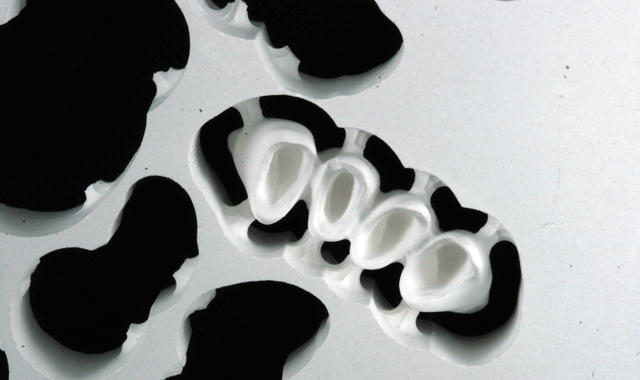

Fig. 1

An 88-year-old man presented for restoration of tooth #25, which was fractured and had been endodontically treated (Fig. 1). A thorough intraoral and radiographic examination was performed, which revealed damage to the remaining anterior mandibular teeth incurred over the years as a result of scaling and curettage (Fig. 2). This damage to the

Fig. 2

root surface of the lower incisors-which was visible on the radiograph (Fig. 3)-is known as “Riffle-ization.” Described by Dr. Riffle as a technique for removing every last bit of calculus during repeated root scaling, what is now known as “Riffle-izing," ultimately-over the years-changes the shape of the neck of the tooth to resemble an hour glass.